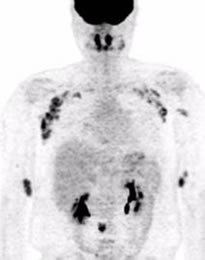

核医学は主に各臓器の機能が評価できる画像診断です。脳血流、心筋血流、肺血流、肝予備能、腎機能、骨代謝などをそれぞれ特殊な放射性医薬品を用いて画像化し評価することができます。CTほど一般的な画像検査ではありませんが、形態的な評価のみならず、臓器の機能評価ができることが大きな利点です。乳癌の最初に転移するリンパ節の検索も、核医学的手法を用いて行っています。また当院では、核医学検査とCTの融合画像(SPECT-CT)も可能です。機能画像とCTの形態画像との融合画像が得られ、診断精度の向上が図られます。また、最新のソフトウェアの導入により、SPECTを用いた定量評価もできるようになっています。

PET(ポジトロン断層画像)も核医学検査のひとつです。当院はサイクロトロン施設であり自前で18F-FDG(フルオロデオキシグルコース)を合成しPET検査を行っています。18F-FDGはブドウ糖に似た物質に放射性物質の18Fを付けたものです。注射をすると、ブドウ糖をよく使う脳・心筋・がんなどに集まります。この薬に使われる18Fは半減期が110分と短いため、すぐに減ってしまいます。そのため、病院内にサイクロトロンという機械を設置して病院内で製造しています。当院ではPETにCTを組み合わせたPET/CT検査を行っています。これによりPETの機能(糖代謝)画像とCTの形態画像との融合画像が得られ、診断精度の向上が図られます。

当施設では年間で核医学検査を約2500件、FDG-PET検査を2000件行っています。

核医学画像は放射線診断専門医により検査・読影され、病院全体の診療に貢献しています。